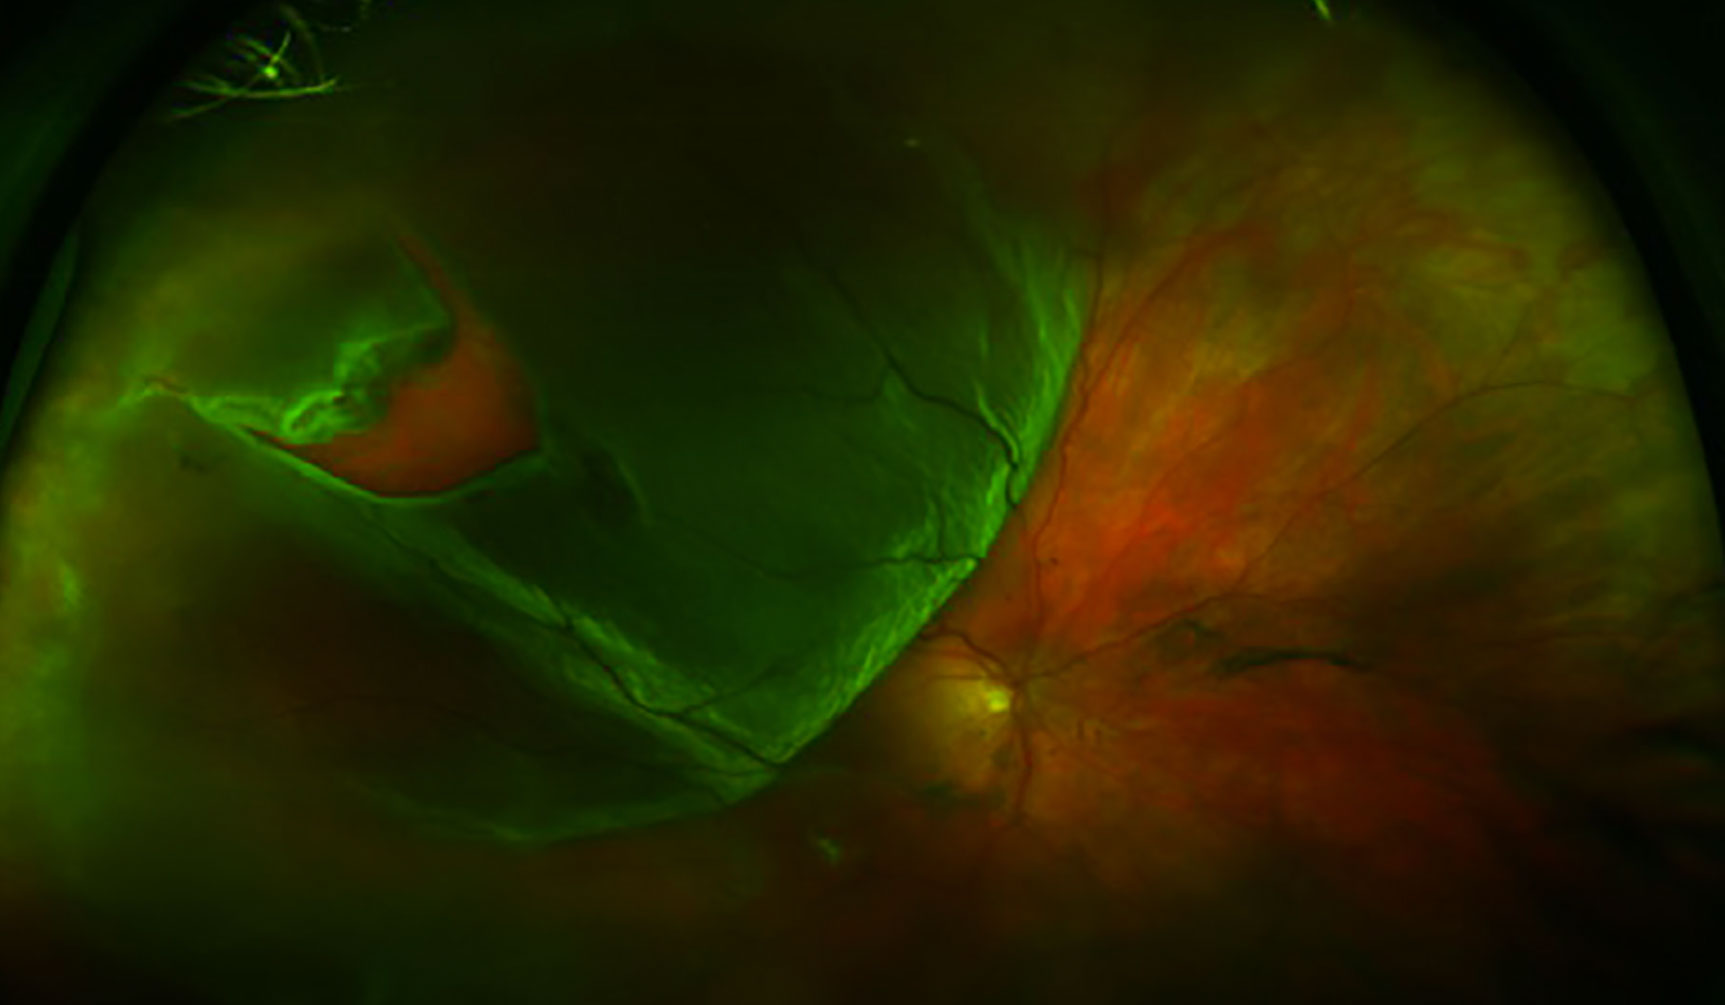

망막 박리를 보여주는 안저 사진

망막 박리를 진단하는 표준 검사는 간접 검안경검사를 사용하여 눈 뒤쪽을 확인하는 산동 안저 검사이다.[4][10][13] 이는 종종 공막 압박이라고 하는 기술을 포함하며, 이는 전체 망막을 명확하게 볼 수 있도록 돕는다.[4][10][14] 눈 앞부분에 대한 세극등 현미경 검사에서도 망막 열공을 나타낼 수 있는 셰퍼 징후라고 하는 작은 색소 입자가 나타날 수 있다.[4][9][10]

망막의 시야가 불분명한 경우, 극광각 안저 사진 촬영, B-스캔 초음파 검사, 광학 단층 촬영법 (OCT)과 같은 영상 기술이 박리를 식별하는 데 도움이 될 수 있다.[4][13][14] 안저 사진 촬영은 눈 뒤쪽을 자세히 보여주며, 망막 열공 또는 파열을 나타낼 수 있다.[4][16] B-스캔 초음파 검사에서 박리된 망막은 일반적으로 유리체강에서 떠다니는 막으로 나타나며, 파동과 같은 움직임을 보인다.[19] OCT는 망막 뒤의 체액, 황반(망막의 중심 부분)의 침범, 망막층 내의 기타 이상을 감지할 수 있다.[4][20]